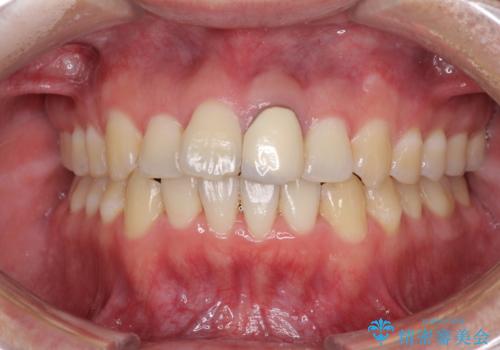

前歯の歯並びとクラウンを改善 インビザラインとオールセラミック

- 前歯の歯並びと不自然な色をした前歯のクラウンを気にして来院された患者様です。

上下前歯の歯列不正はインビザラインにより歯列を整え、その後に、前歯をオーダーメイドタイプのオールセラミッククラウンにて補綴治療することとしました。

初診時には、歯並びを整えることのみを検討されていましたが、歯列が整うにつれて不自然な色合いが気になるようになり、矯正治療を行ってから補綴治療をする計画を受け入れてくださいました。

口元の印象が明るく変わり、患者様には大変満足していただきました。